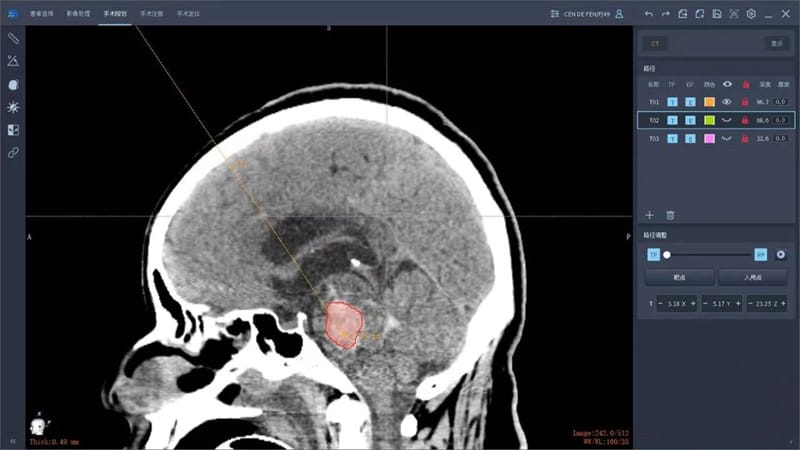

主任医师徐溥澄接诊后,对手术治疗方案进行讨论,考虑到常规开颅脑干血肿清除手术难度大、术后创伤大,经决定应用手术机器人行精准穿刺脑干血肿抽吸引流术;同时,考虑到患者中脑导水管受血肿推压,已出现脑积水征象,决定同时行侧脑室穿刺置管外引流术。

做好充分的术前准备,徐溥澄带领手术团队将CT及MRI影像数据传输到机器人导航系统中,进行融合重建,利用机器人导航系统合理规划手术路径。术中,依据机器人导航系统在机器人机械臂的引导下,经头皮穿刺完全抽出脑干血肿,精准避开了颅内大小血管及重要脑功能区。